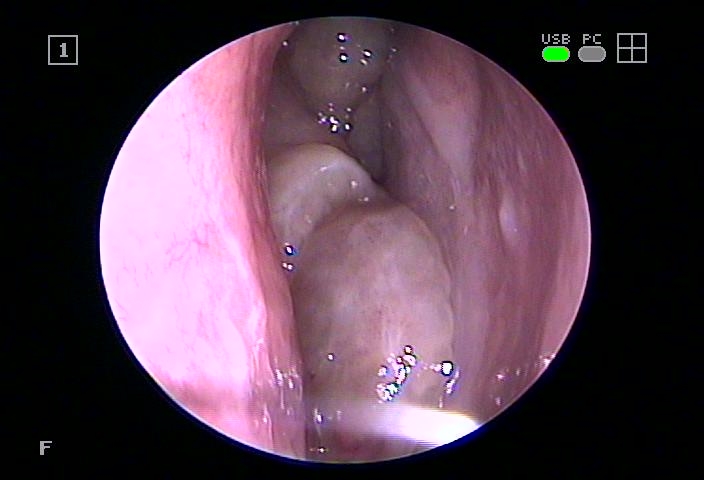

비중격만곡증이라고도 불리는데, 코의 중간벽이 굽어지면서 양쪽이 다른 면적을 가지고 있는데, 이때 염증으로 수축되어 더욱 악화되는 모습을 보입니다.

내부에 존재하는 농도가 충분히 배출되지 않아 고여 있기 때문에 직접 개발한 카테터를 이용하여 구석구석 제거하여 순환과 환기를 도와드리고 있습니다.